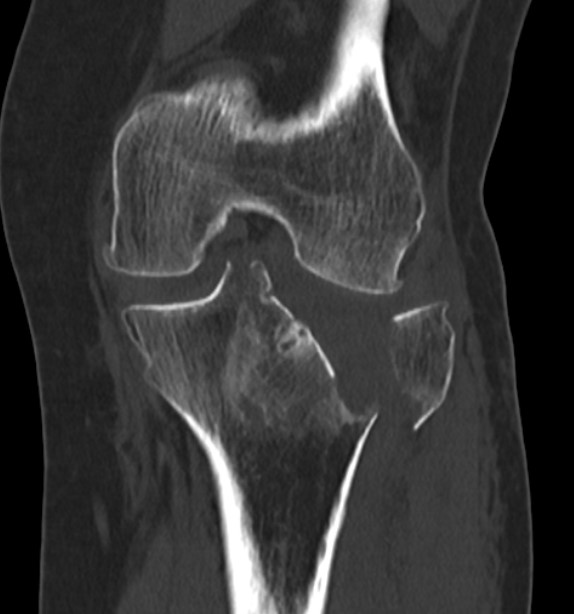

3 column concept of tibial plateau fractures

Luo et al. Orthop Trauma 2010

- introduces the 3 column concept

- medial column / lateral column / posterior column

- posterior column can be splint into medial and lateral fragments (posterolateral / posteromedial)

- imporant as any surgery must address these fragments

- typically require additional posteromedial or posterolateral approaches

https://pubmed.ncbi.nlm.nih.gov/20881634/